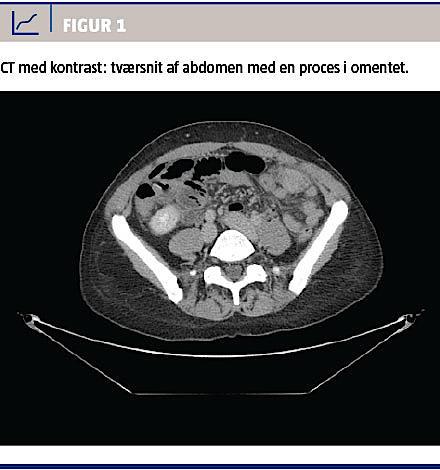

Ved en gynækologisk undersøgelse fandt man normale forhold med en spiral in situ. De vitale parametre var upåfaldende. En biokemisk undersøgelse viste normalt hæmoglobinniveau, basisk fosfatase og negativ S-humant choriongonadotropinniveau, men forhøjet C-reaktivt proteinniveau til 16 mg/l og alaninaminotransferaseniveau på 77 E/l. En CT af abdomen med i.v.-kontrast viste en atypisk inflammatorisk proces i venstre side af abdomen (Figur 1 og Figur 2), og der blev udført diagnostisk laparoskopi på mistanke om inflammeret Meckels divertikel. Ved laparoskopien fandt man i omentum majus en solid tumor, som var adhærent til forreste bugvæg. Efter at man havde sikret sig, at der i øvrigt var normale forhold intraabdominalt, blev tumoren laparoskopisk fjernet en bloc. Makroskopisk vurderet var tumoren 45 × 40 × 20 mm. På snitfladen var den fast heterogen med fedtvævslignende områder og nekroselignende forandringer centralt. Ved mikroskopi af omentet påvistes Actinomyces med karakteristiske sulphur granules bestående af bakterier og inflammatoriske celler (Figur 3). Dyrkning af ascitesvæske og podning fra IUD og cervix viste ingen vækst af Actinomyces. Efter konstatering af Actinomyces fik patienten fjernet spiralen og blev sat i i.v.-behandling med penicillin 5 mio. IE × 4 dagligt i 13 dage, efterfulgt af otte dages behandling med clindamycin 900 mg. Derefter blev patienten behandlet med amoxicillin 750 mg × 3 dagligt.